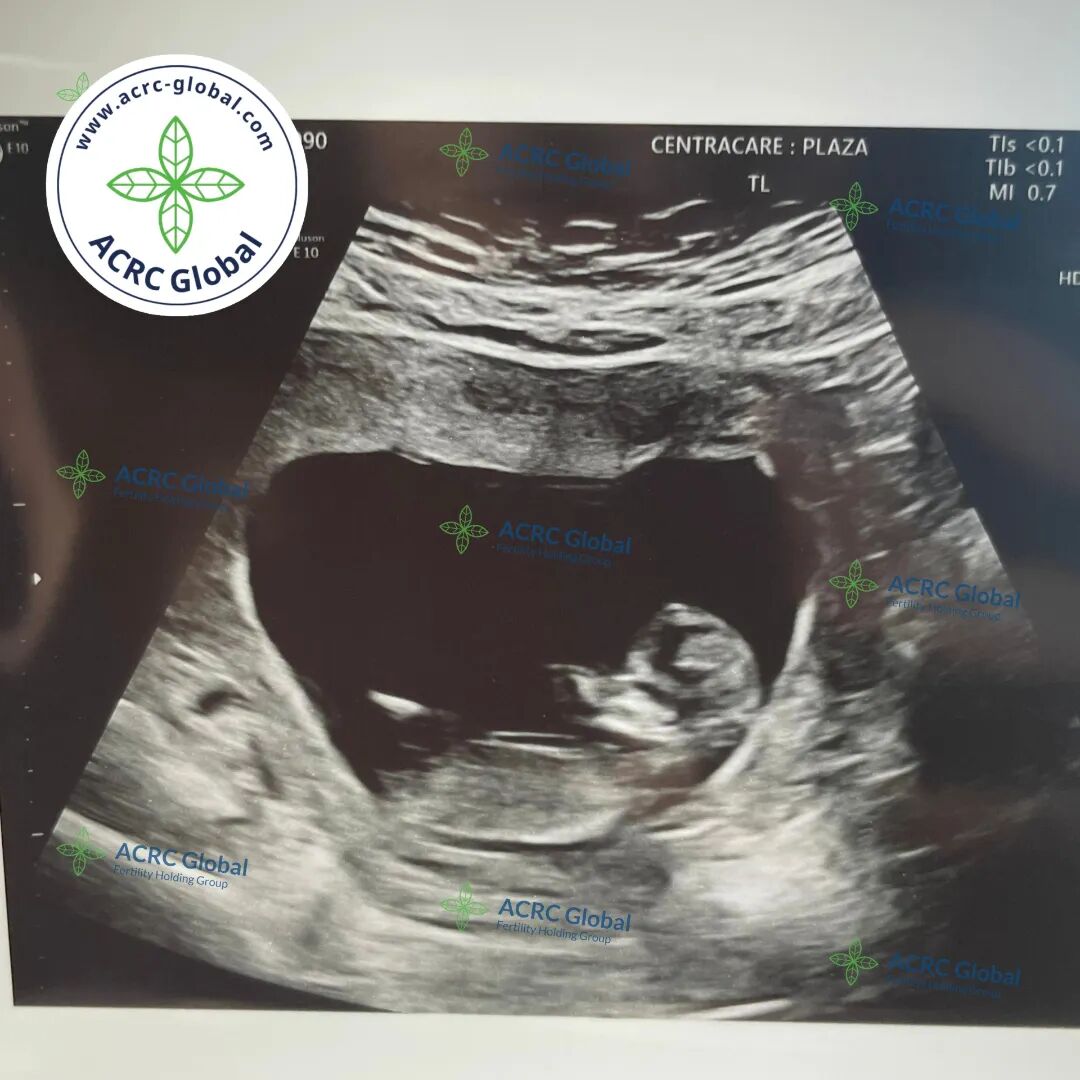

爱妈J12周B超体检更新!胎宝宝已经达到了柠檬的大小,身体比例逐渐变得更为协调,体重约为14克左右。12周的胎儿正处于一个关键的发展阶段,许多器官已经开始形成并开始运作。胎儿的手指和脚趾开始分开,小小的面部特征也更加明显,心脏的跳动依然强劲。